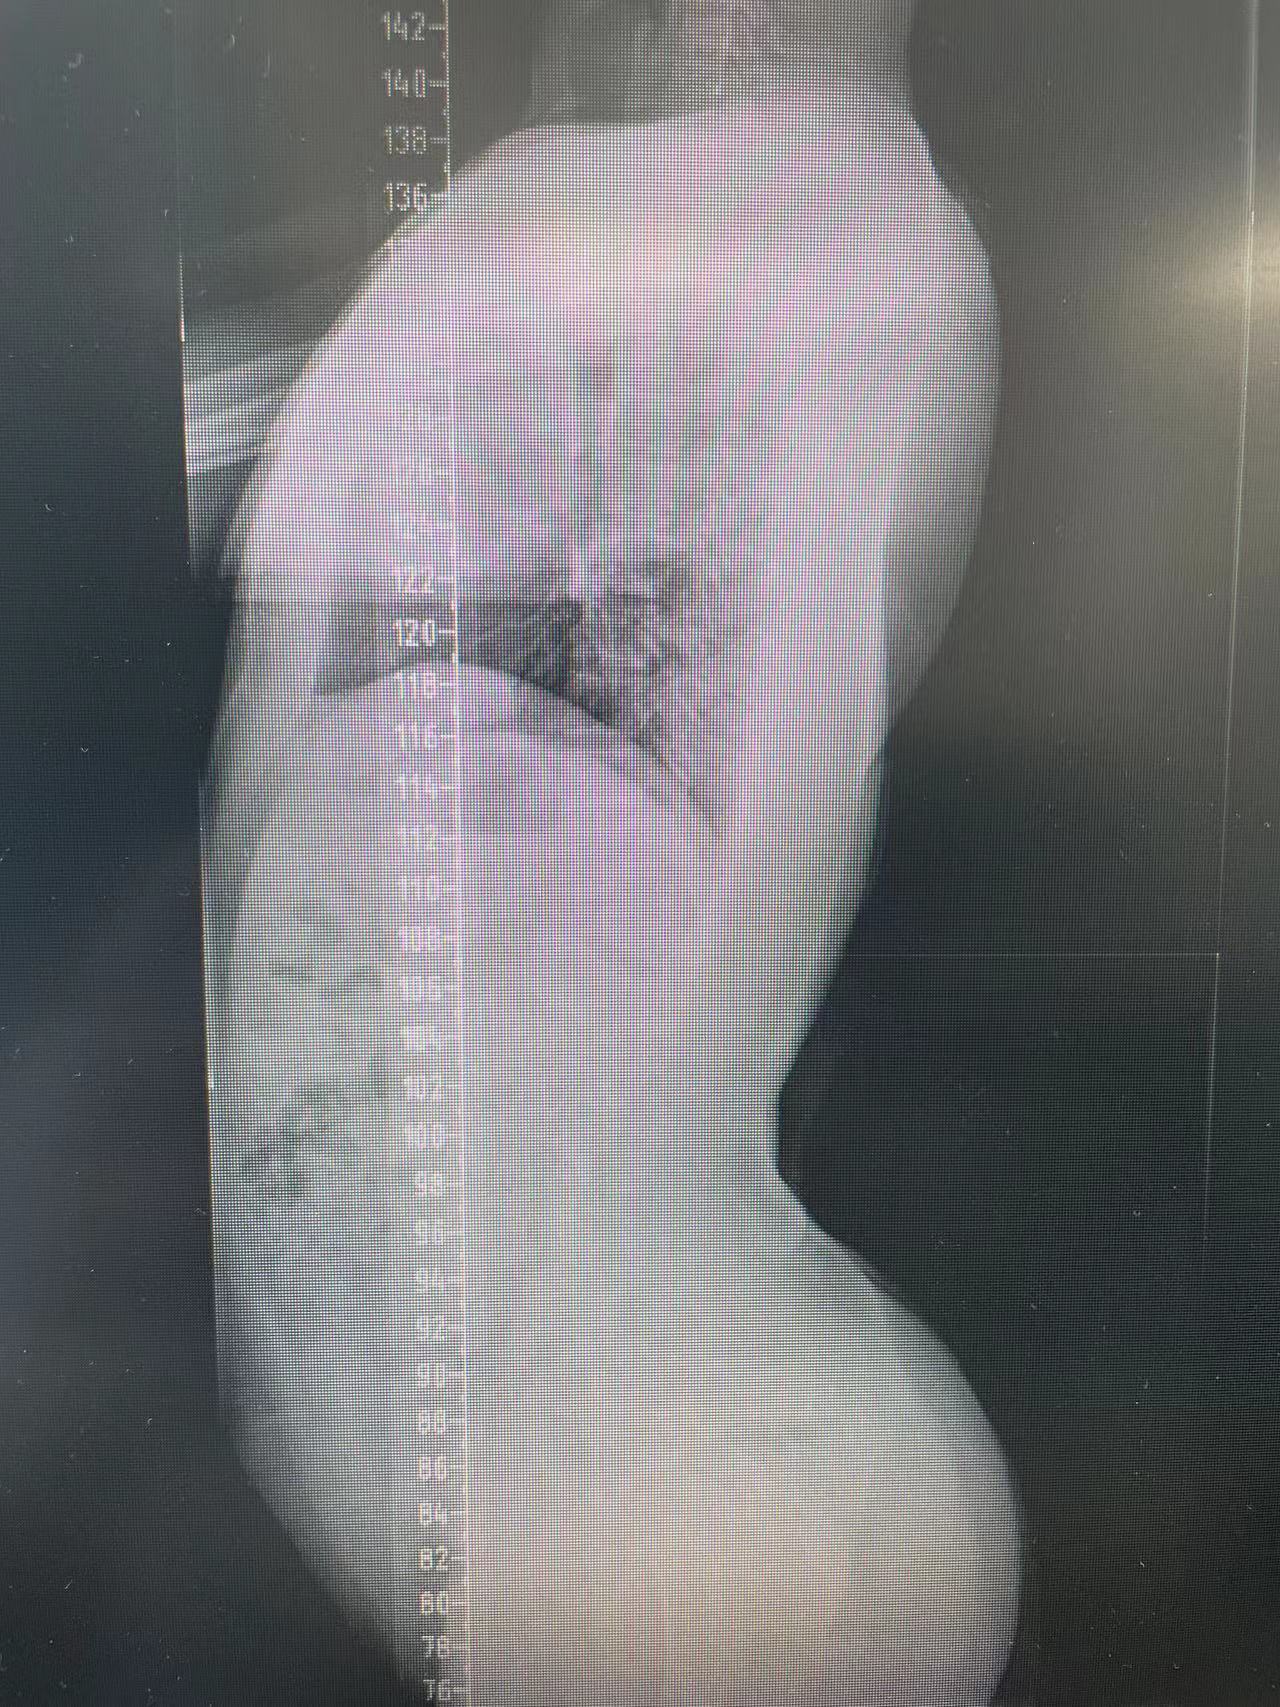

患者杨某,15岁,一年前在家中行走不稳,未及时给予系统治疗,现双下肢僵硬、无力症状明显,影响正常生活,遂前来我院脊柱外科中心D区接受住院治疗。

脊柱外科中心D区辛大奇、王东海、孙洪岩医疗团队完善患者术前检查后,明确诊断为胸12半椎体侧后凸畸形,经过积极与胡侦明教授沟通、讨论后,共同为患者制定手术方案,为患者施行先天性脊柱侧弯、半椎体侧后凸畸形截骨矫形+植骨融合内固定术。